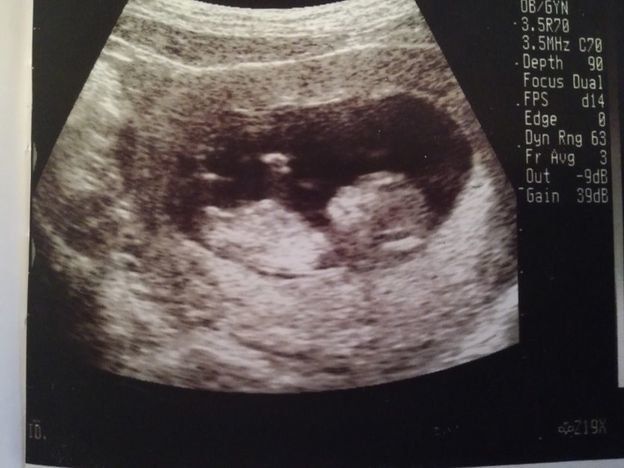

妊娠12週目のエコー写真

上の二つの画像は、同じ日に撮ってもらったもの。人の形になっている赤ちゃんの姿を確認して、体に衝撃が走りました。エコー画像上で、小さい体をモゾモゾと動かしている様子も見られて、本当にかわいらしく、感動して少し目が潤んでしまいました。人の姿として確認できる画像でしたので、夫に見せても、実家に帰省して両親に見せても、みんな「おぉー!」と喜びの声を上げていました。